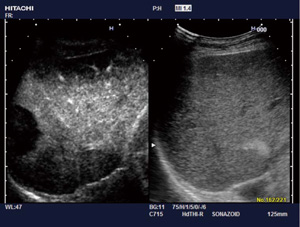

3.HI REZ(High Resolution Imaging)

専用の高速ASIC(特定用途向けIC)演算器と超高速アルゴリズムを用いて,リアルタイムに数万回の空間画像処理を実施する高精細画像適応型フィルタ技術である(図4)。超音波画像特有のアーチファクトであったスペックルノイズを低減し,より明瞭な組織構造を表示してコントラスト分解能を向上させる。 |

図4 HI REZ |